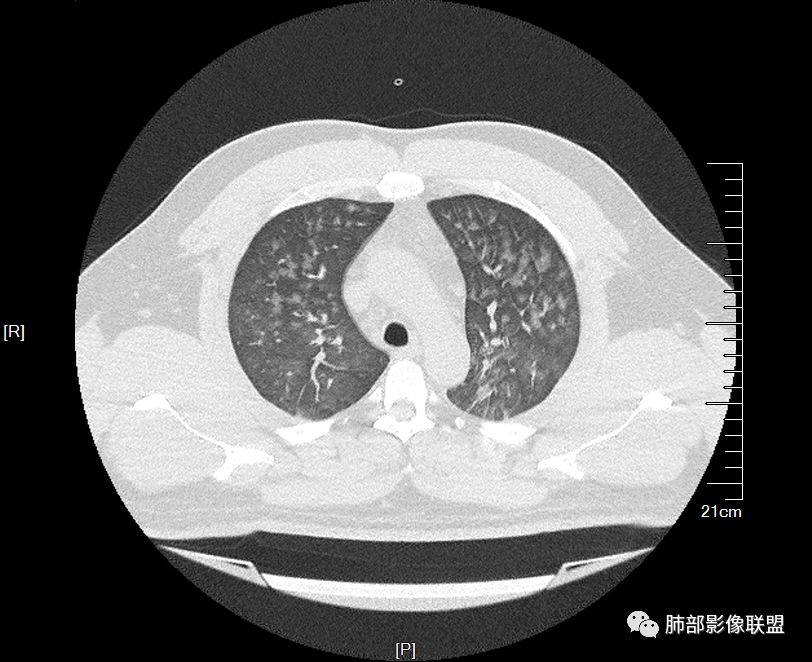

双肺多发弥漫性磨玻璃结节影,大小不一,形态不规则,部分融合,支气管未见明显扩张,部分血管束略增粗,叶裂胸膜增厚,临床有痛风,左足痛6天,考虑:1:痛风结节(一般实性结节,很少磨玻璃结节影)2:血管炎?3:病毒性肺炎(水痘-疱疹肺炎?)

双肺多发腺泡结节及磨玻璃,小叶间隔增厚(大网格状),腺泡结节内及磨玻璃内可见细网格影(小叶内间隔增厚),影像表现符合肺泡出血改变,血肌酐升高,考虑肺肾综合征。鉴别肺水肿。

两肺弥漫向心分布的腺泡结节,部分融合,两肺小叶间隔增厚,血肌肝高,考虑肺泡性肺水肿

青年男性,痛风、肾功能不全病史,双肺多发结节状、斑片状阴影,支气管血管束增粗,可见支气管袖口征,叶间裂及小叶间隔增厚,考虑肺水肿。

年轻男性,既往血肌酐升高,左足痛六天入院,有痛风及高血压病史。CT示双肺多发磨玻璃结节影,不规则,部分融合成团或片状,小叶间隔增厚,以双下肺为明显,叶间胸膜亦见增厚。考虑为1.Good-Pasture综合征。2.病毒性肺炎?3.肺水肿?

年轻男性,痛风史,高血压史,肌酐高,左足痛6天入院。胸CT:双肺多发弥漫性磨玻璃结节影,大小不一,部分融合,上中下肺都有,中内带多,胸膜下少。部分血管束略增粗,小叶内间隔、小叶间隔增厚,下肺明显,左室大。叶裂胸膜增厚。临床有痛风,左足痛6天,考虑:心衰、间质性肺水肿?弥漫性肺泡出血?鉴别:MPA,肺肾综合征,痛风结节等。

青年男性,有肾功能不全史和痛风史,这个影像分布有个典型的特点,全部是以中央间质周围的渗出性改变,这个改变主要就是两种可能,一种是肾功能不全导致的血管通透性增高导致的肾性肺水肿,一种是出血导致的DAH改变,具体是哪种,影像上不好简单的鉴别,需要结合更多临床资料综合分析。

年轻男性,痛风,肌酐高,提示肾功能有损,两肺多发磨玻璃腺泡结节,小叶间隔增厚,双侧少许胸水,血管增粗,考虑肾性肺水肿,DAD,鉴别肺肾综合征,需要更多临床资料

小叶间隔增厚,无明显重力趋势

少量积液,脂肪肝

这里有一点重力趋势

中轴间质增厚,小叶间隔增厚,小叶内间质增厚,部分重力作用,双侧对称,胸水,按理淋巴道回流受阻有

肺水肿类病变有

问题是腺泡结节如何解释?